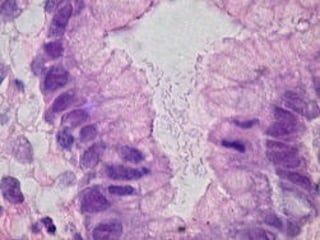

• 1. Chronic superficial gastritis, which is an

inflammation of the stomach lining due to the

infiltration of lymphocytes, plasma cells,

eosinophils, and monocytes into the mucosal

lining of the stomach, which causes injury to the

gastric glands.

• Histologic analysis of biopsy. Routine Histologic

analysis of biopsy samples is common and practical.

Helpful also to visualize the mucosa, permitting detection

of Histologic gastritis and lesions such as MALT-type

lymphomas.